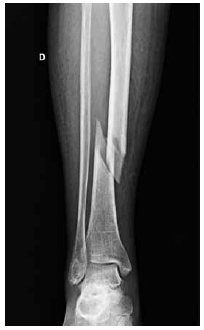

M.W.C., feminino, 87 anos. Após queda da própria altura, passou a apresentar dor e impossibilidade para caminhar. A radiografia do membro inferior direito é mostrada a seguir.

Assinale a alternativa correta.

Em relação às fraturas de fêmur proximal, assinale a alternativa correta.